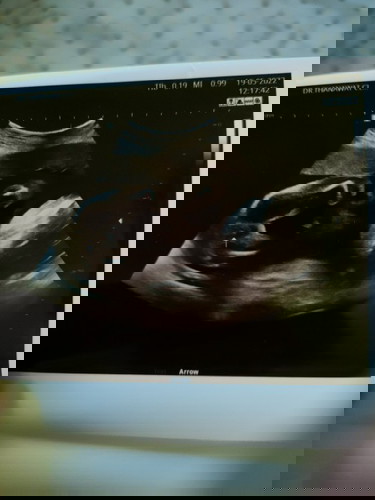

บ้านนี้คุณหมอบอกลูกสาว98% ลูกศรชี้2กลีบมาเชียว แม่ดูไม่ค่อยเป็นแต่ก็เขื่อหมอค่ะเพราะอยากได้ลูกสาวจ้า